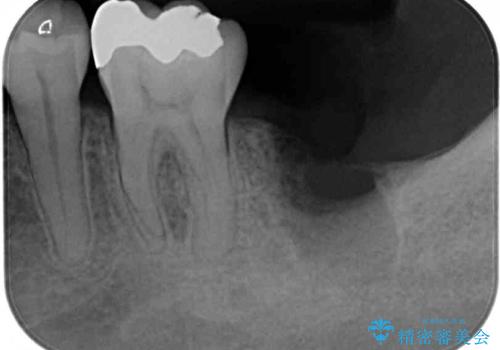

- 左下の奥歯に違和感を感じて来院された患者様です。

診察をした結果、歯根にまで及んだ虫歯と歯周病による著しい骨欠損が認められ、抜歯をせざるを得ない状況でした。